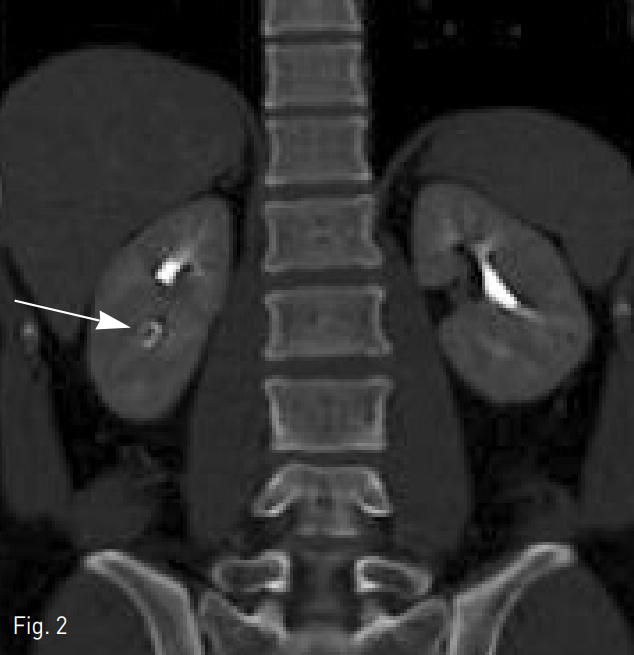

신장 CT에서 병변이 보이는 부위인 오른쪽 중간 뒤쪽 신배 부분에 혈관 공급을 하는 두 개의 엽간 동맥에서 PVA foam particles (COOK Incorporated., Bloomington, US) 와 microcoil (Tornado, COOK Incorporated., Bloomington, US)로 초선택적 색전술을 시행했다. 시술 후 시행한 신동맥 조영술에서 신장 실질의 15~20 % 정도 혈관 공급이 줄어들고 나머지 신장 실질은 정상적으로 혈류가 공급되는 것을 확인했다 (Fig. 4).

Fig. 4

Post embolization renal artery angiography shows decreased parenchymal ladening of posterior lower segment of right kidney (arrows).